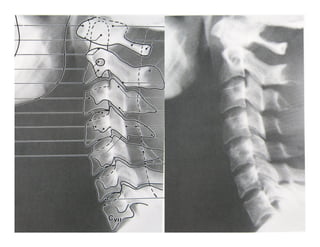

LINEAS REFERENCIALES

§  1.-Línea vertebral anterior: a lo

§  2.-Línea vertebral posterior: limita

§  3.-Línea espinolaminar: limita el

§  4.- Línea espinosa posterior: se

§  5.- Línea clivus-odontoidea: